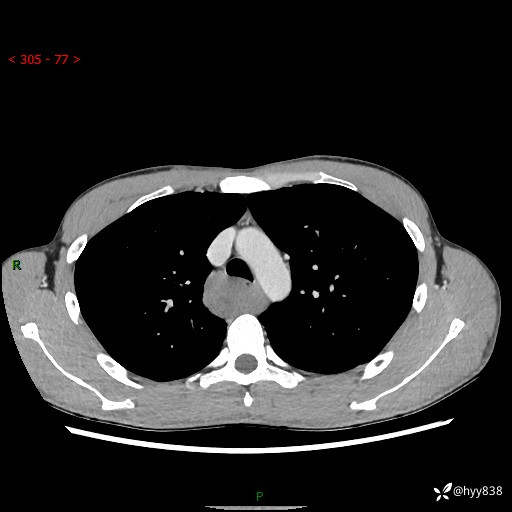

年轻男性,发现后纵隔占位1周余。征象简单,难在定位---结果公布~

现病史:患者于1周前体检行检查发现后纵隔占位,患者平素无明显咳嗽咳痰,无心慌、胸闷、胸痛、呼吸困难、低热、盗汗,无头痛、头晕,无腹痛、腹胀等不适。现患者欲求进一步治疗,遂来我院就诊,以“纵隔占位”收入我科。 患者自起病以来,精神可,睡眠可,饮食可,大小便正常,体重无明显改变。

胸部CT平扫+增强